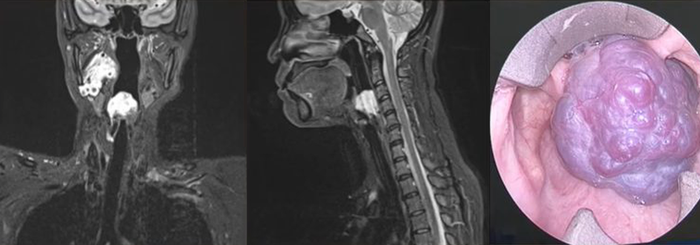

Ca bệnh được ThS.BS.CKII Nguyễn Trương Khương trình bày tại hội nghị là một trường hợp u máu lớn chiếm toàn bộ lòng thanh quản, gây khó thở và vướng khi nuốt - những triệu chứng dễ nhầm lẫn với các bệnh lý thông thường của đường hô hấp trên.

Hình ảnh khối u máu chiếm trọn thanh môn, không thấy cuốn và dây thanh (Ảnh: BVCC)

"Đây là một trong những ca phẫu thuật khó và hiếm gặp, khi ranh giới giữa đường thở và lưỡi dao chỉ cách nhau vài milimét, đặc biệt khi người bệnh lại có tiền căn thay van tim và dùng thuốc chống đông. Chỉ một sai sót nhỏ cũng có thể gây chảy máu nghiêm trọng và đe dọa tính mạng. Vì vậy, ca mổ đòi hỏi sự chuẩn bị kỹ lưỡng, tính toán chính xác từng thao tác và phối hợp nhịp nhàng giữa các chuyên khoa", bác sĩ Khương chia sẻ.

Trước phẫu thuật, người bệnh được ngưng thuốc chống đông 5 ngày và mở khí quản chủ động để đảm bảo an toàn đường thở. Suốt nhiều giờ phẫu thuật, bác sĩ Khương cùng ê-kíp đã sử dụng đốt điện hai cực kết hợp dao siêu âm nhằm cắt triệt để khối u, hạn chế tối đa mất máu và bảo tồn cấu trúc thanh quản.

Sau phẫu thuật, người bệnh hồi phục tốt, chức năng nói, nuốt và hô hấp hoàn toàn bình thường. Kết quả này không chỉ thể hiện trình độ phẫu thuật chính xác, mà còn là minh chứng cho năng lực xử lý những ca bệnh phức tạp của đội ngũ y bác sĩ Bệnh viện ĐKQT Nam Sài Gòn.